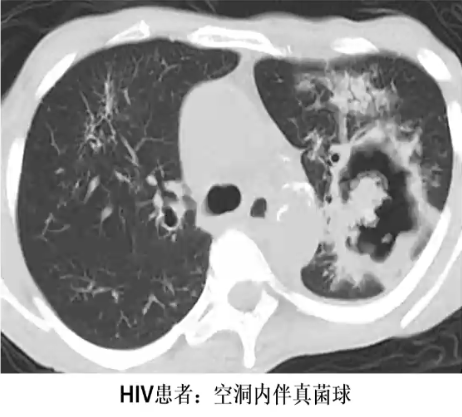

半侵袭性曲霉菌病

❖ 单侧或双侧、上叶为主斑片影和胸膜增厚

❖ 经数周、数月或数年进展为空洞

❖ 中心坏死物与周围分离形成空气新月征

❖ 最终形成厚壁空洞伴或不伴软组织密度影(真菌球)

❖ 类似于曲菌球,但其壁为自身坏死后形成,并非先前存在